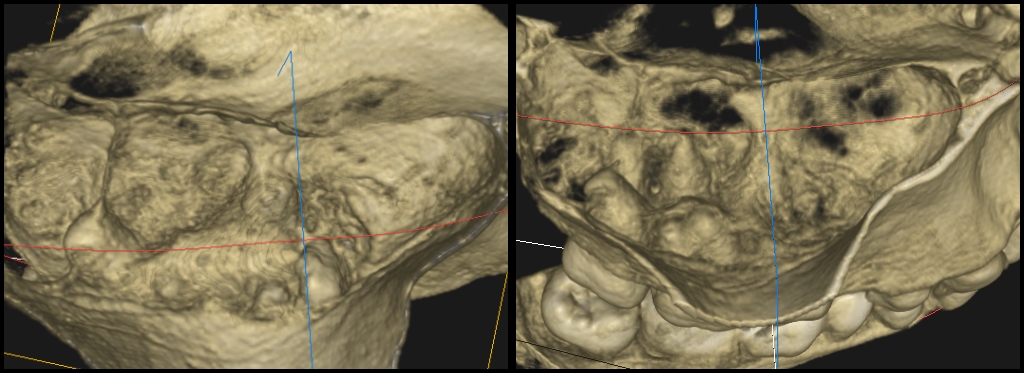

Minęły 4 lata. W marcu 2020 roku pacjent zgłosił się z innym problemem i przy okazji wykonałem tomografię leczonego wcześniej zęba. Rezultat terapeutyczny przedstawiają ryciny 7‑10. Widzimy na nich całkowitą remisję zmiany i powrót fizjologicznej pneumatyzacji zatoki szczękowej w danym miejscu.

Ryc. 7. CBCT – porównanie obrazów zmiany w płaszczyźnie strzałkowej przed i po leczeniu.

Ryc. 8. CBCT – porównanie obrazów zmiany w płaszczyźnie czołowej przed i po leczeniu.